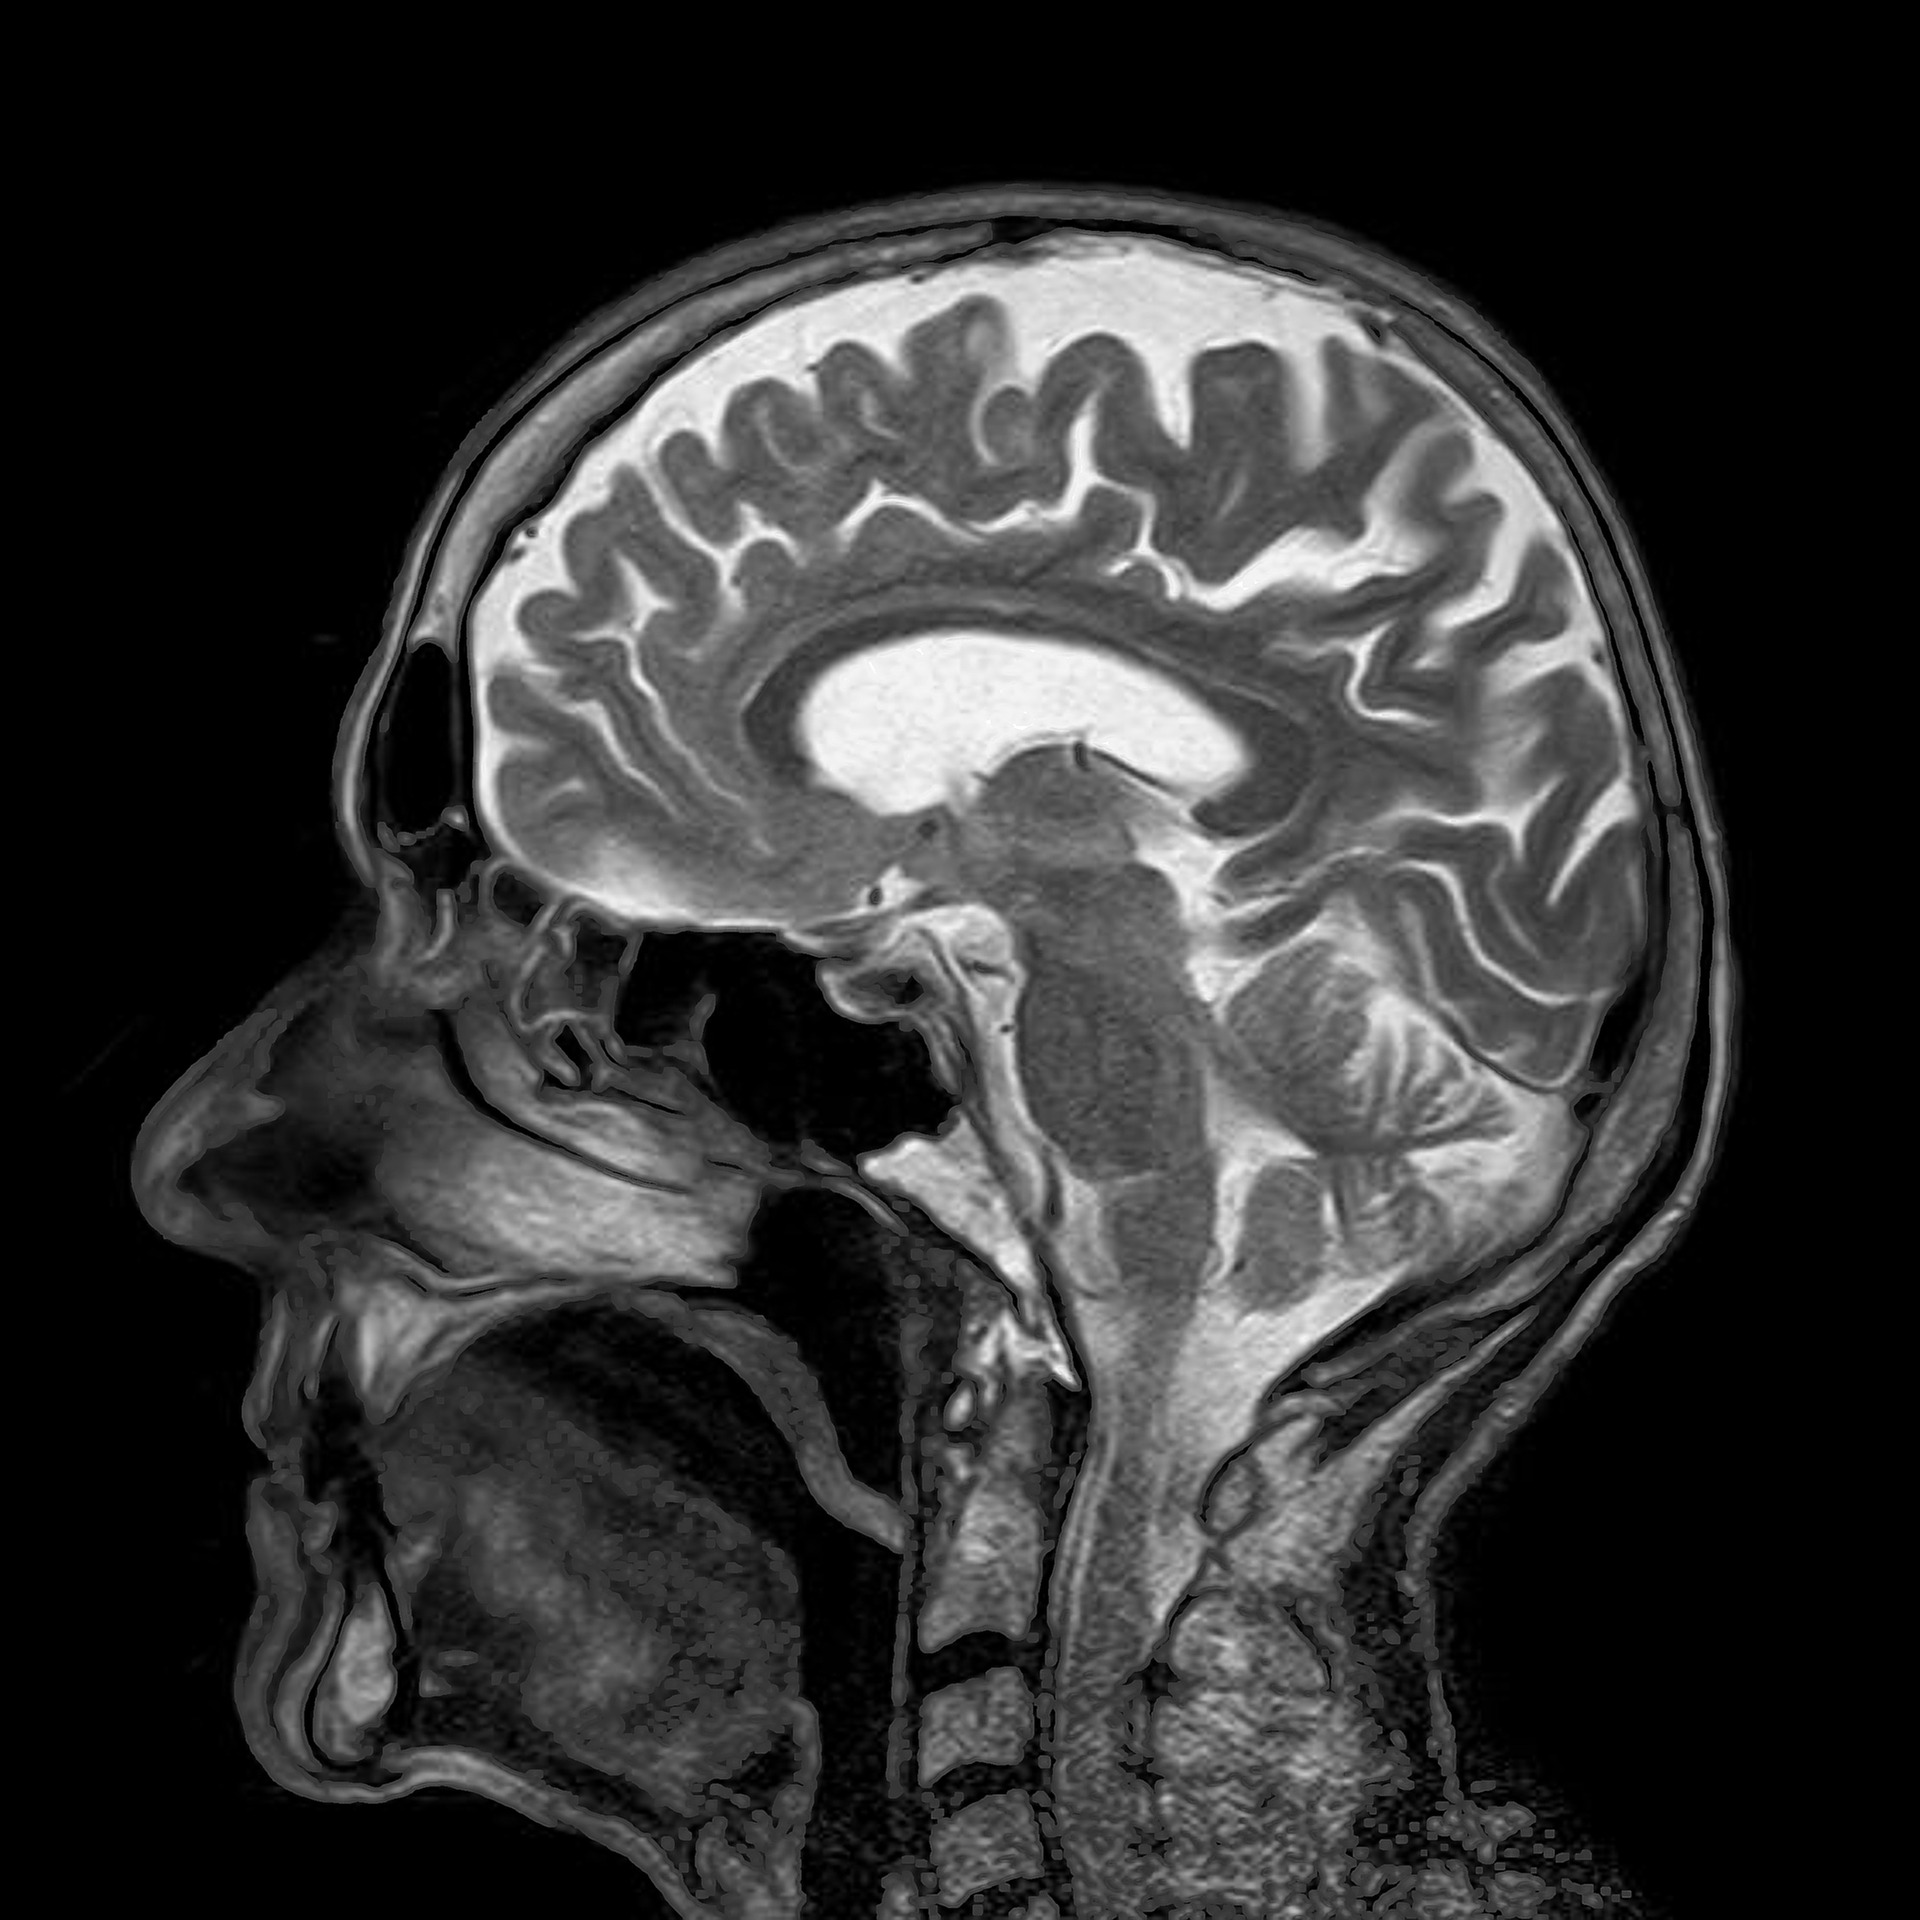

Justo cuando tu cuerpo empieza a flojear demasiado, tu cerebro hace sus mejores esfuerzos para preparar a tu consciencia para el gran salto. En sus momentos finales muchas personas (y esto está científicamente demostrado) tienen experiencias extracorpóreas, un encuentro con parientes en un lugar tranquilo, un sentimiento de mejor conexión con el universo y, por supuesto, ven la clásica luz brillante al final del túnel. Pero, ¿Qué está ocurriendo realmente?

En el momento que empiezas a estar clínicamente muerto, tu cerebro entra en quinta, con una explosión de electricidad y un pico de actividad a través de muchas de sus regiones, y empieza a liberar neuroquímicos que lo excitan mucho más de lo normal. Este es el momento en que todas las experiencias de «la luz blanca y brillante» ocurren. Otro estudio, sugiere que aquellos que han tenido una ECM (Experiencia Cercana a la Muerte) tienden a ver las mismas cosas, aunque puedan variar un poco en función de las creencias culturales y religiosas de cada uno.

- Una experiencia extracorporal, normalmente en la forma que estás flotando encima de tu lecho de muerte. Posiblemente causada por el daño causado por la falta de oxígeno al enlace temporoparietal.

- Reunion con lo familiares y amigos muertos, a veces con antepasados que nunca conocimos en vida. O también visitar un extraño mundo y conocer seres hechos de luz. La falta de oxígeno en el cerebro podría ser la causante de estas alucinaciones.

- Una luz brillante al final del túnel. El sistema visual se sobreexcita y se inunda de dióxido de carbono, volviéndose más sensible a la luz. También se pueden acentuar otros sentidos en un corto espacio de tiempo.